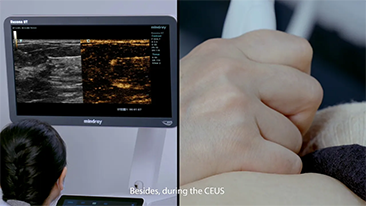

La gamme d'imagerie gÊnÊrale Resona de Mindray aide les cliniciens à obtenir des rÊsultats de diagnostic plus prÊcis et des traitements plus efficaces gr?ce à une gamme de sondes complète et à des outils cliniques avancÊs efficaces.